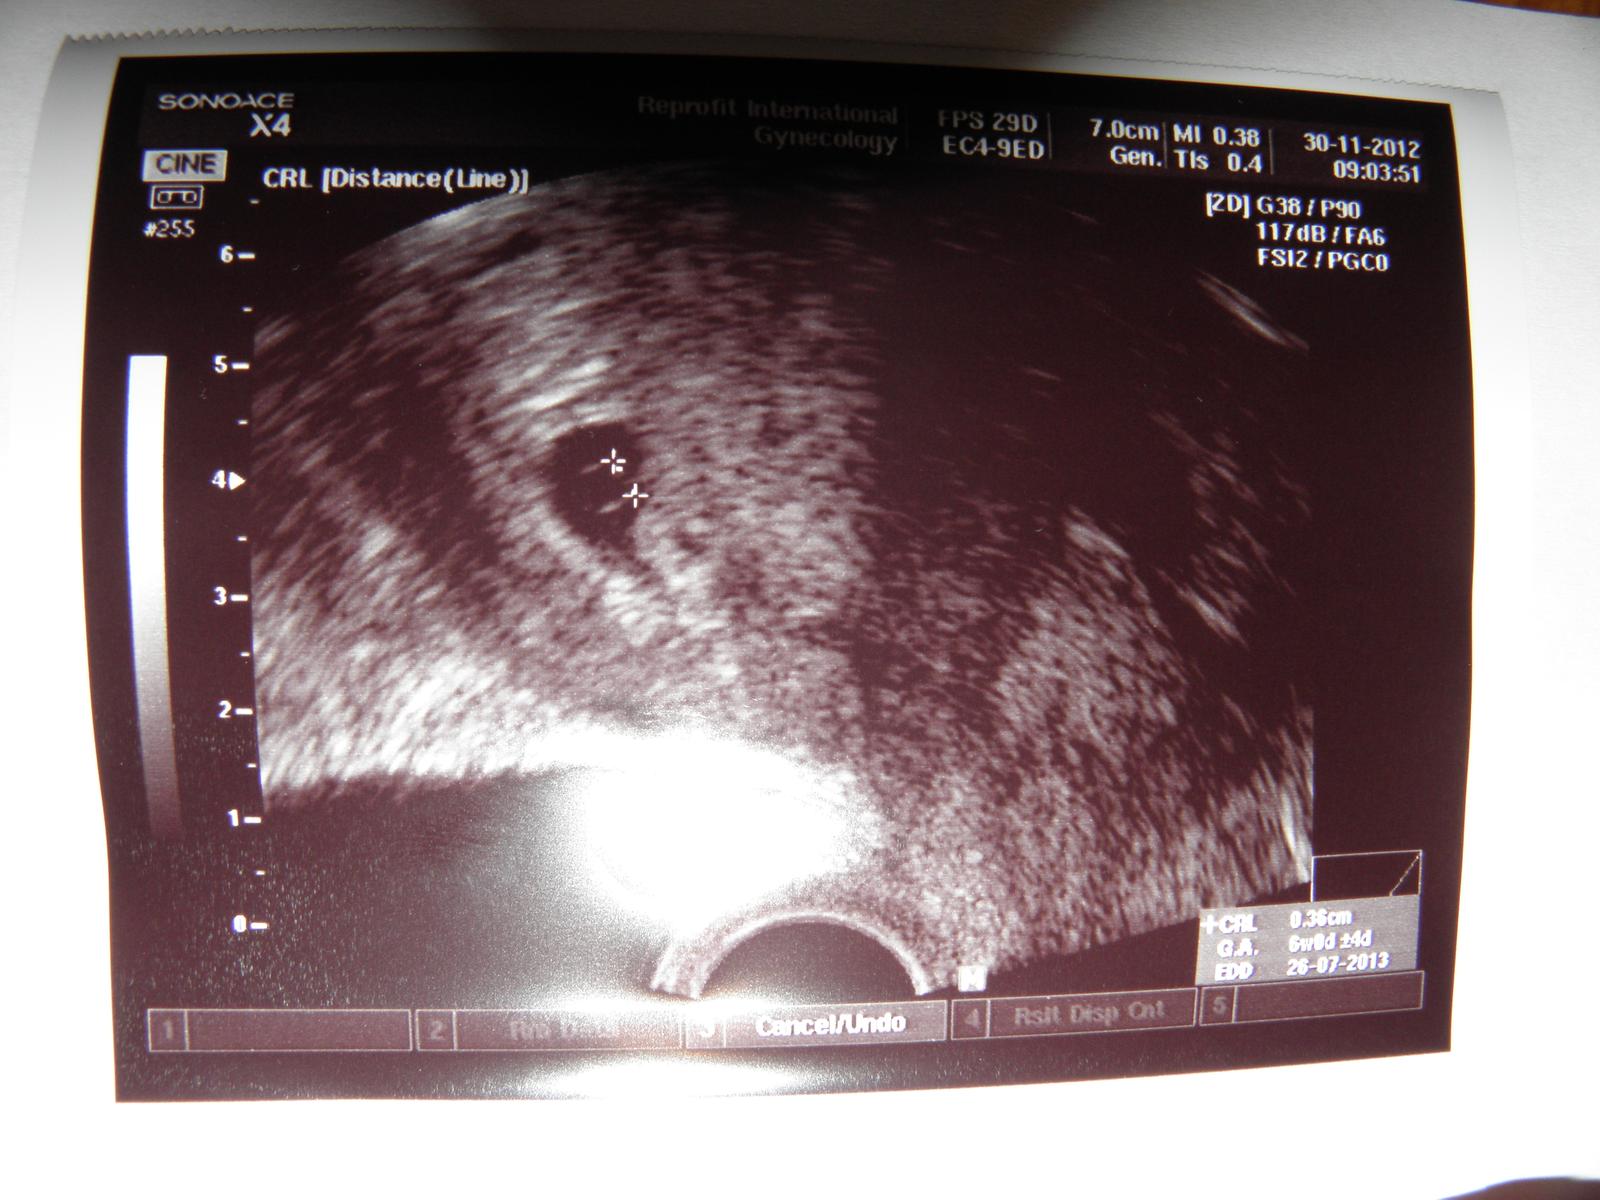

takze ja uz som doma z brna, mame 1 gestacny vacok so slabou akciou a druhy gestacny vacok vstrebavajuci sa. Cize druhe babulko to vzdalo. Dr. povedala ze je to pozitivne, ale nemame este vyhrane, ze akcia je slabsia a pomalsia ako by mala byt. Kontrola o 2 tyzdne. Myslela som ze mi odlahne, dalsie 2 tyzdne vsak budem v strese ci je babulko ok. Priznaky tehu nemam takmer ziadne. Baby ja sa priserne bojim o drobciatko, aby to nevzdalo ked sme to dotiahli az sem. Som vdacna za srdiecko, ale strach je obrovsky